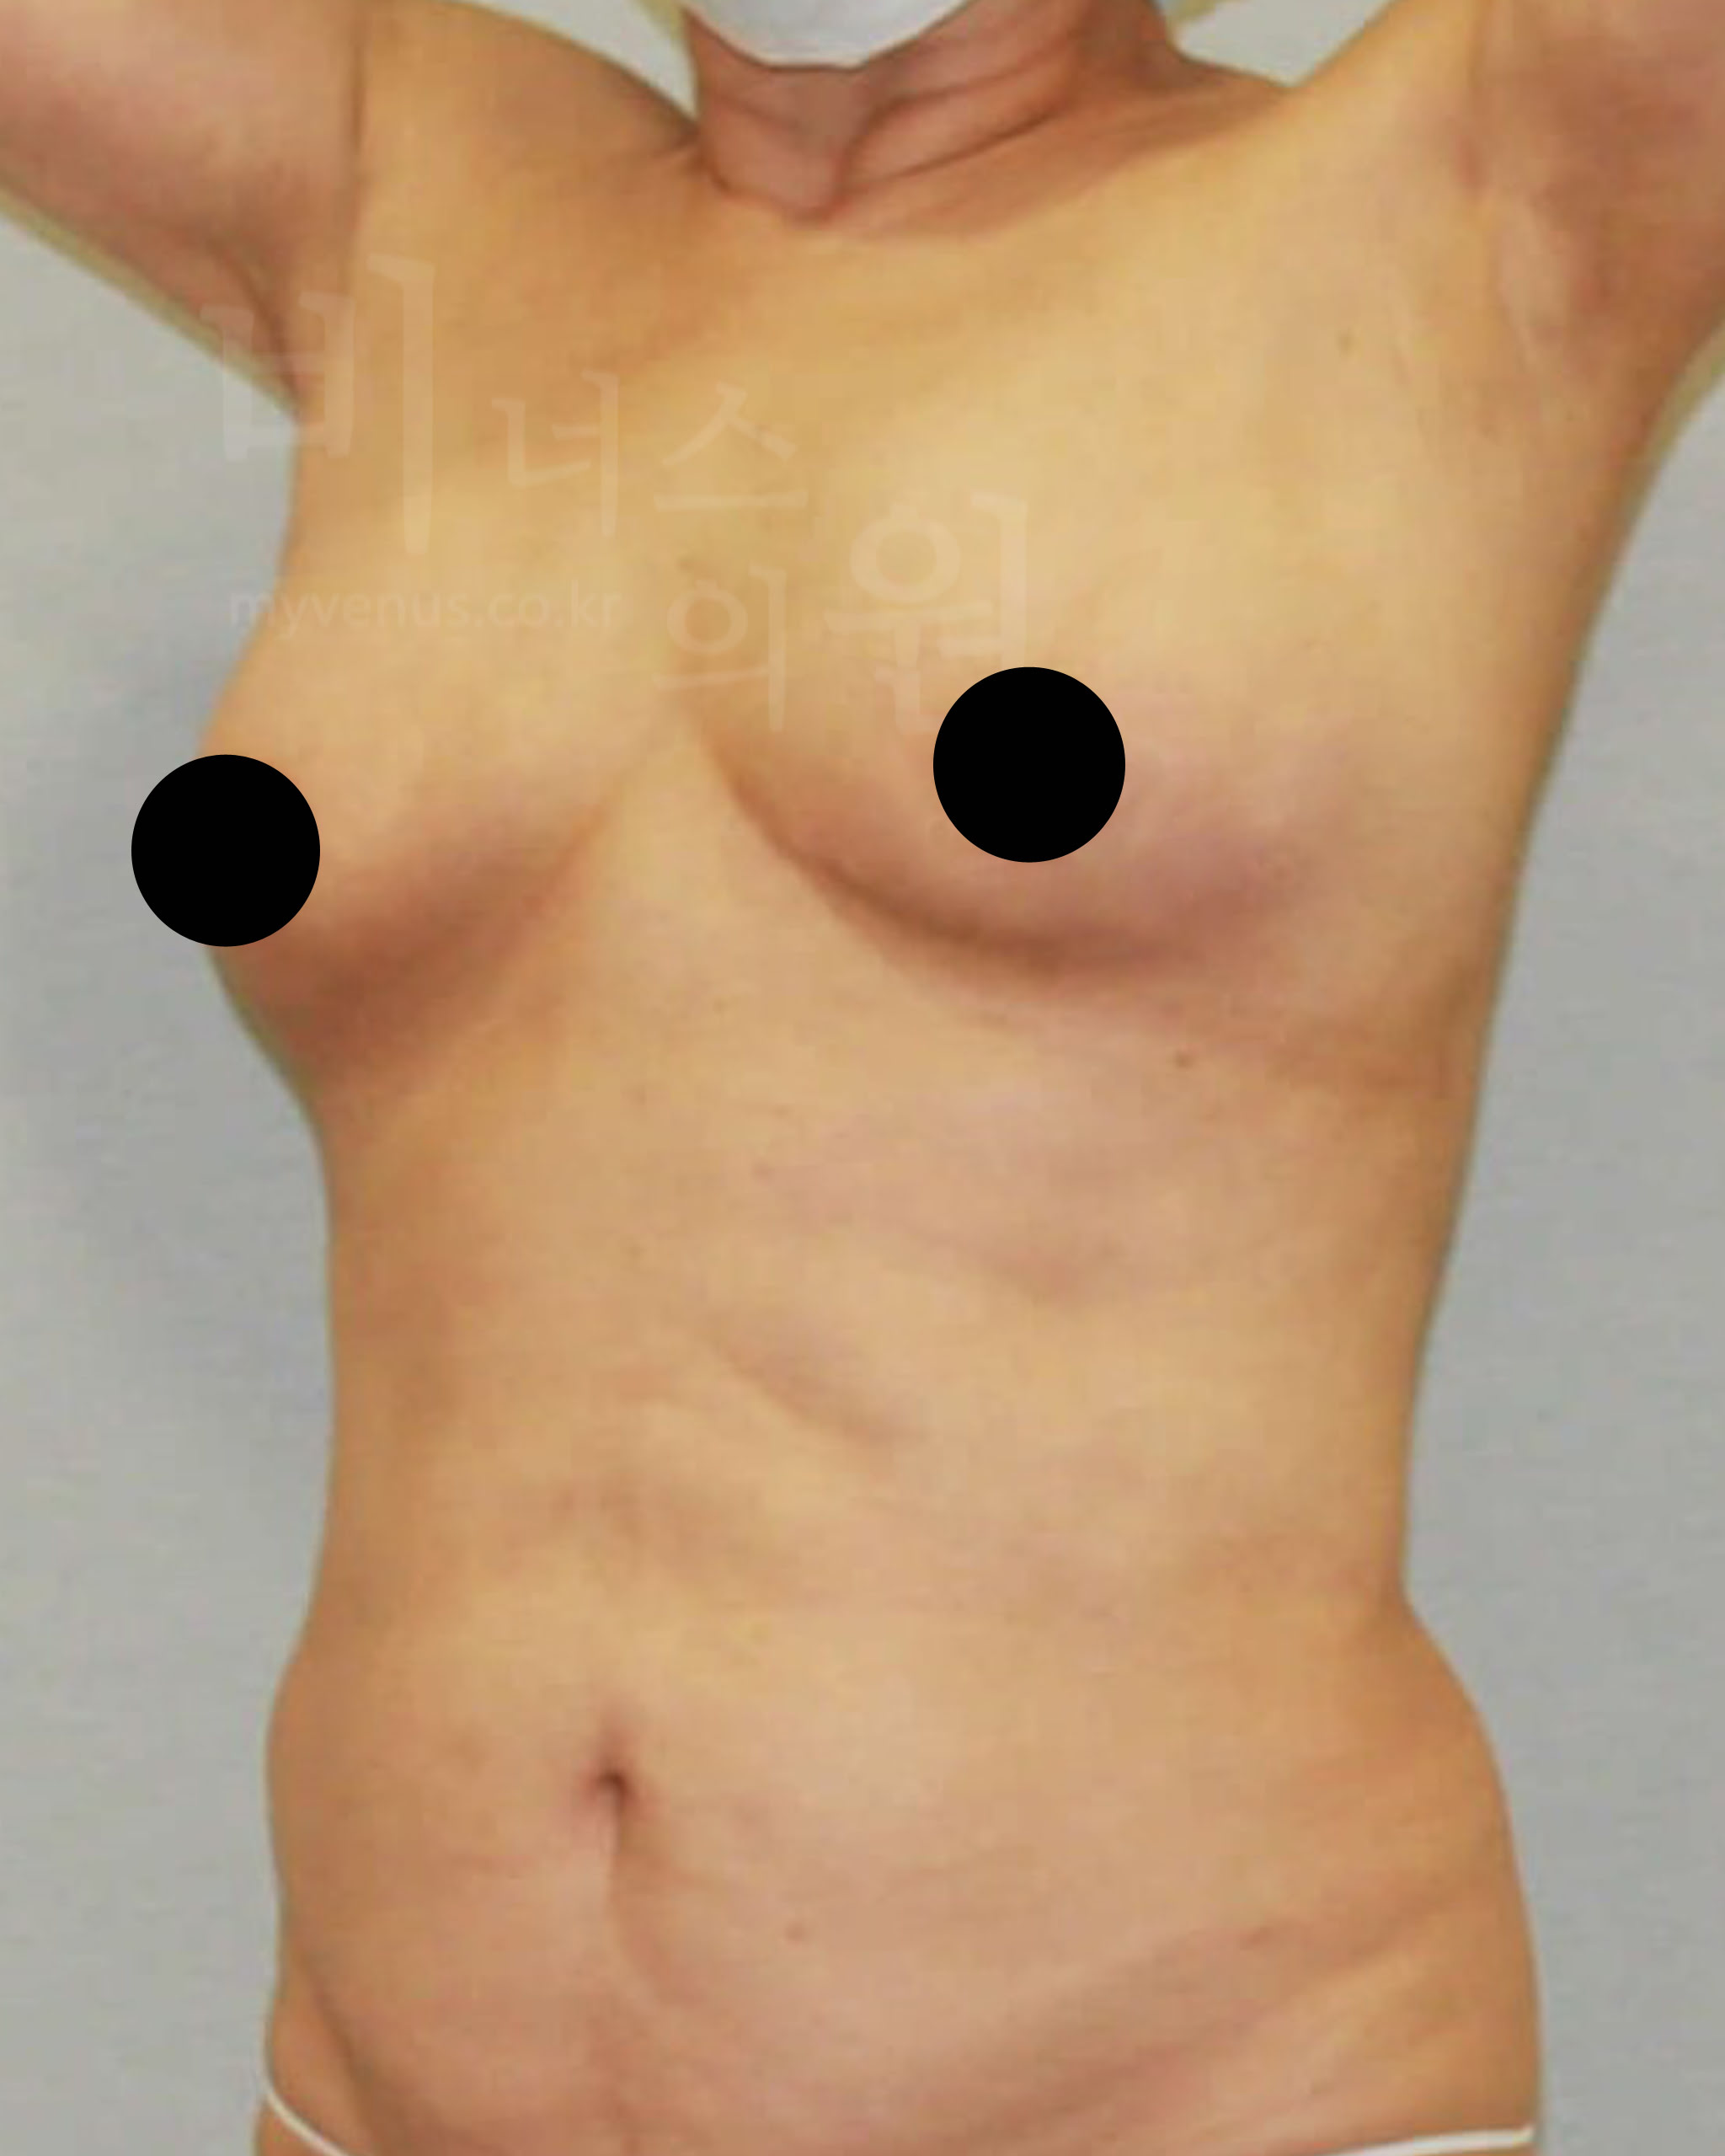

가슴축소 지방흡입 전, 한달 후 경과 사진으로 보는 효과

수술 부위 - 가슴 축소, 부유방, 겨드랑이, 유방 옆구리 지방흡입

가슴축소 지방흡입 전 사진

유방이 처지고 몸에 비해 큰 가슴 모습

가슴축소 지방흡입 후 사진

처짐 없이 사이즈가 감소와 리프팅 된 모습

젊은 여성분으로 무겁고 처진 가슴의 사이즈 감소를 위해 내원해 주셨어요. 가슴축소 지방흡입 후 가슴 사이즈가 주었으며, 처짐 없이 볼륨 업 된 가슴을 확인할 수 있어요. 가슴뿐만 아니라 부유방, 겨드랑이, 유방 옆구리 지방흡입을 함께 함으로써 주변 부위와 어색함 없어요.

가슴축소 지방흡입 전 사진

처진 정도가 유방 길이로 보여지는 모습

가슴축소 지방흡입 후 사진

사이즈 감소와 유방 길이가 짧아진 모습

가슴축소 지방흡입은 저렴한 비용으로 흉터나 수술 후의 부작용, 합병증 걱정 없이 큰 가슴의 고통에서 벗어나 볼륨 있고 예쁜 가슴을 만들 수 있어요. 측면의 모습에서 가슴 안쪽의 유방 선이 길게 늘어져 있던 모습이였으나 처짐 없이 볼륨 업된 사이즈 감소가 이루어지면서 가슴 선이 짧아 졌어요.